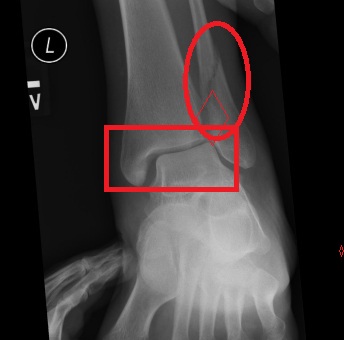

Stress ray ankle ankles left broke michelle both. Heel pain foot ankle diagnosis aafp afp 1015

Thomas o¿donnell: soldier whose leg was shattered by a taliban bullet. Diagnosis of heel pain